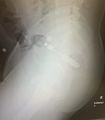

- Abdominal xray

- Demonstrate position, shapes, and number of foreign bodies

- Demonstrates possible presence of free air (perforation of rectum or colon)

- Perf of rectum below peritoneal reflection shows extraperitoneal air along psoas

- Perf above peritoneal reflection reveals intraperitoneal free air under diaphragm